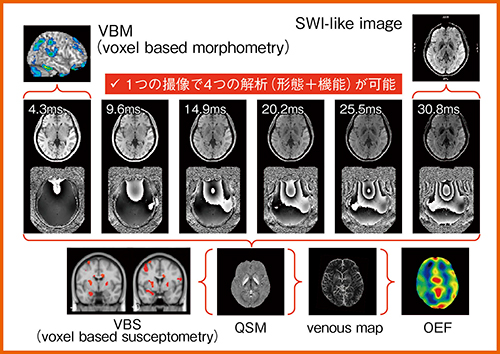

ADのMRI診断は,内側側頭葉の萎縮を視覚と画像統計解析(voxel based morphometry:VBM)で評価する方法で行われているが,われわれの研究ではVBMとQSMを組み合わせることで,より早期に精度の高い診断を行うことをめざしている。研究にあたり日立は,一度の撮像でVBMやQSM,SWI,静脈マップ,OEFなどさまざまな解析が可能なハイブリッド撮像法を開発している(図2)。

図2 QSMとVBMのハイブリッド撮像法(W.I.P.)